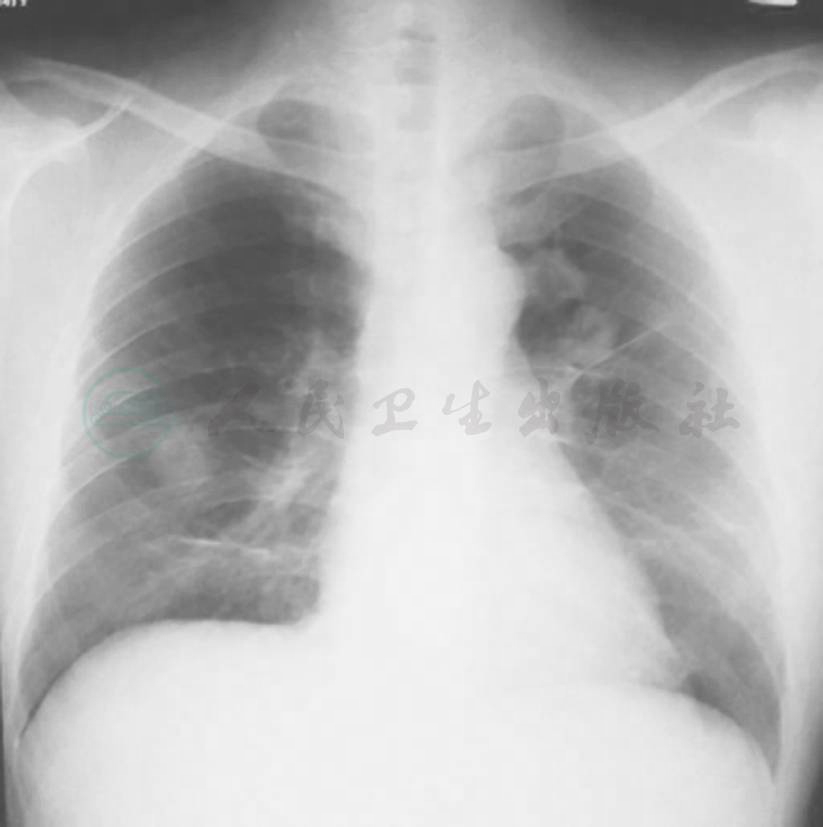

系列胸部影像学检查表现见图1~图5。

图1 X线胸片(2009-11-04)

X线胸片示左下叶斑片影,右上肺纹理增多

图2 X线胸片(2009-11-11)

X线胸片示左下叶斑片影较前明显吸收

图4 X线胸片表现(2009-11-17)

X线胸片示双肺多发结节影

3.胸部影像学特点为病初见左下肺斑片影,莫西沙星治疗后肺部阴影吸收,停用后肺部阴影短期内再次增多。